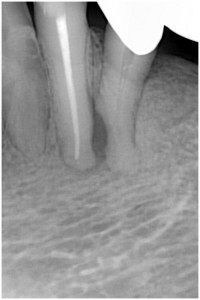

歯髄壊死 右下の前歯 川口の歯科 歯医者 さかえ歯科クリニック

2014年12月16日